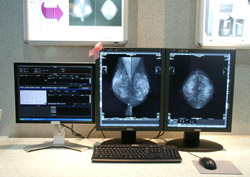

「Infinet-Mammo」は,マンモグラフィ専用に設計・開発された画像診断ワークステーション。乳房の自動位置合わせや,スキンラインの自動検出機能を有する。(株)ナナオと東京特殊電線(株)のモニタが採用されており,10bit階調以上の濃淡表現が可能でアナログフィルムに迫る画質を誇る。また,同じ被検者の過去と現在の画像を比較読影できるプロトコールが新しく追加された。読影医ごとに登録が可能で,画像の配置を各自が使用しやすいようにカスタマイズできる。検診用の所見レポート画面にも改良が加えられた。入力項目を必要最低限のものに絞り,速さと効率の良さが求められる検診において入力時間の短縮を実現している。

「Infinet-Mammo」